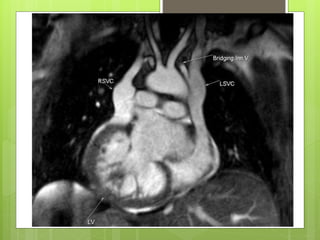

PERSISTENT LSVC